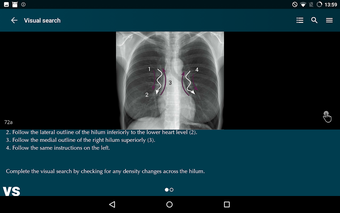

Radioloji'yi Keşfet: Göğüs Röntgeni Yorumlama, göğüs röntgeninin yorumlanmasının anlaşılmasını artırmak için tasarlanmış bir eğitim uygulamasıdır ve doktorlar, tıp öğrencileri ve radyologlar tarafından kullanılması amaçlanmaktadır. Uygulama, en küçük detayları görüntülemek için yakınlaştırılabilecek yüksek kaliteli görüntüler ve her bulgunun önemini anlamanıza yardımcı olacak bir sesli yorum içerir.

Uygulamanın amacı, kullanıcıların farklı x-ışını bulgularını ve bunların bir hastalığın teşhisinde nasıl kullanılabileceğini daha iyi anlamalarına yardımcı olmaktır. Uygulama, göğüs röntgeni yorumlaması için gerekli çeşitli yapı taşlarını kapsayan 5 bölüme ayrılmıştır.

Ayrıca, uygulama bir hastanın göğüs röntgenini incelemeleri sırasında başvurabilecekleri bir dizi nasıl yapılır içerir. Uygulamadaki nasıl yapılır adımlarını takip ederek, kullanıcılar birçok farklı bulguyu doğru bir şekilde tanımlayabilecekler ve her birini bir hastalığın teşhisi için nasıl doğru bir şekilde kullanacaklarını öğrenebileceklerdir.